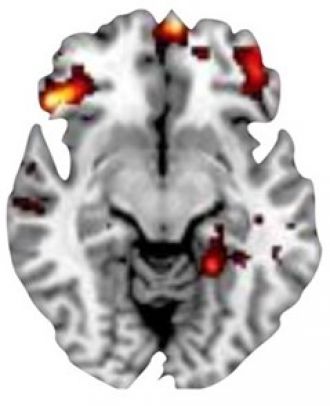

The MRI scans showed different patterns of activity in the brain for adolescents with OCD, compared to healthy adolescents. The differences were particularly strong in the OFC, a region of the brain responsible for decision-making, behavioural control and other cognitive functions.

In participants with OCD, specific areas of the OFC were hyperactive and others were hypoactive during the two decision-making tasks. These findings are consistent with previous research in rats, providing evidence of the specific OFC areas responsible for these psychological functions.

The researchers also found that for adolescents with OCD, hyperactivity of the OFC during the experiments was linked to the severity of OCD symptoms. This further supports the connection between decision-making performance and the disorder.

MRI scan showing hyperactivity of orbitofrontal cortex (OFC)